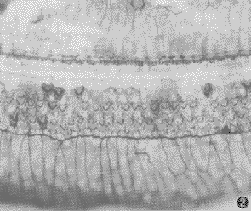

骨髓象:骨髓穿刺常為"乾抽",若穿刺成功可見漿細胞增多,髓系列細胞減少,尤以粒細胞減少為甚,淋巴細胞相對增多。骨髓塗片中毛細胞出現率與外周血象基本相同。而骨髓活檢結果可見較多的毛細胞浸潤,呈散在分布,一般不見分裂象。嗜銀染色可見纖維增生,在細胞間可見到厚而較緻密的網硬蛋白增加,為造成骨髓"乾抽"的原因。